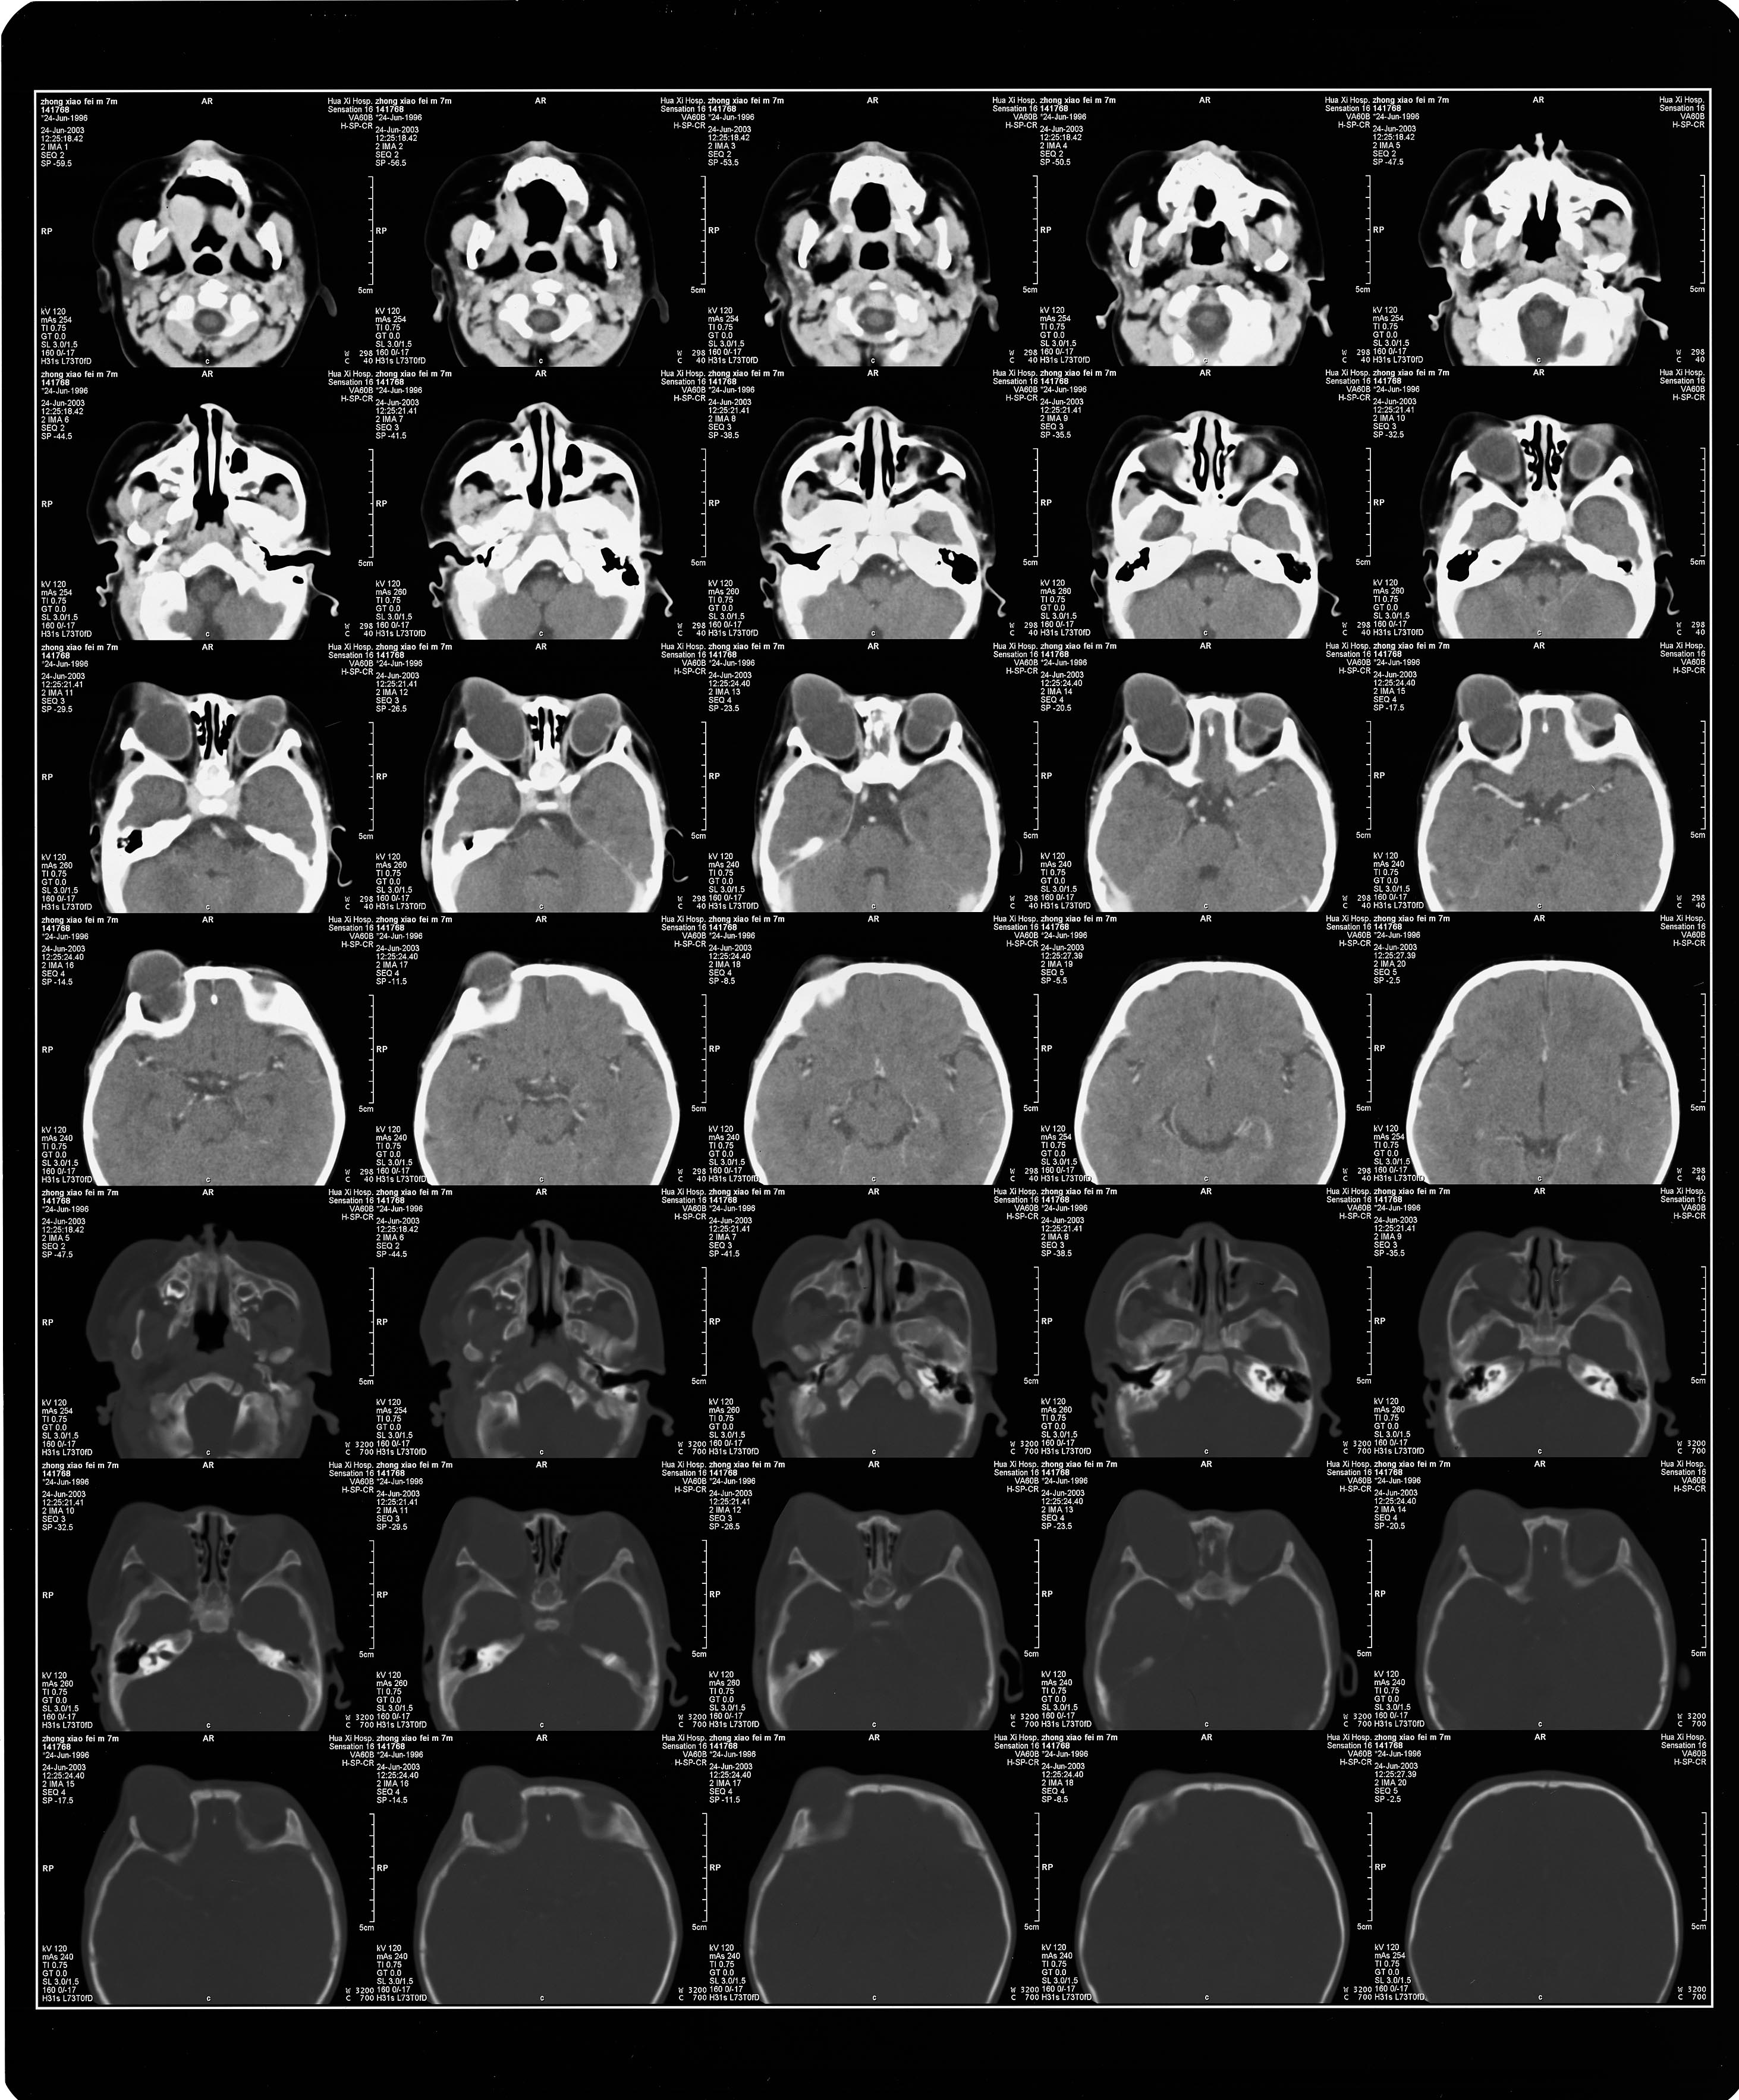

C  T:     双侧眼球增大,形态不规则,成分叶状,并向前突出.双眼晶体未显示,右眼视神经未显示.(见附图CT)

附上ct图片